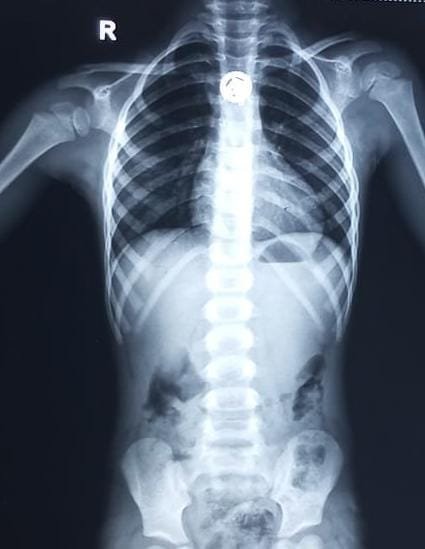

உணவுக் குழாயில் சங்கிலி டாலர் சிக்கிய 3 வயது குழந்தைக்கு அறுவை சிகிச்சை, மயக்க மருந்து இல்லாமல்…

உணவுக் குழாயில் சங்கிலி டாலர் சிக்கிய 3 வயது குழந்தைக்கு அறுவை சிகிச்சை, மயக்க மருந்து இல்லாமல் எடுத்து குழந்தையை காப்பாற்றி சாதனை

மகாத்மா காந்தி நினைவு அரசு மருத்துவமனையில், திருச்சி

ஸ்ரீரங்கத்தைச் சேர்ந்த 3 வயது ஆண் குழந்தை,…